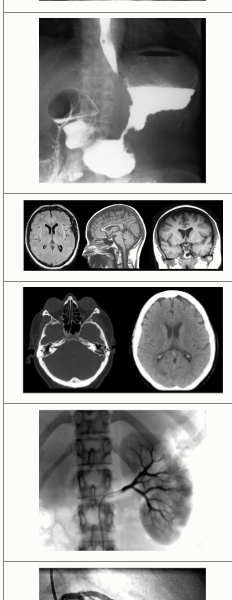

Задания 32: Установите соответствие между фотографией и методом медицинского исследования определённого органа.

Коронарография

МРТ головы

Почечная ангиография

Рентгенография желудка с контрастированием

Обзорная рентгенография брюшной полости

Компьютерная томография головы